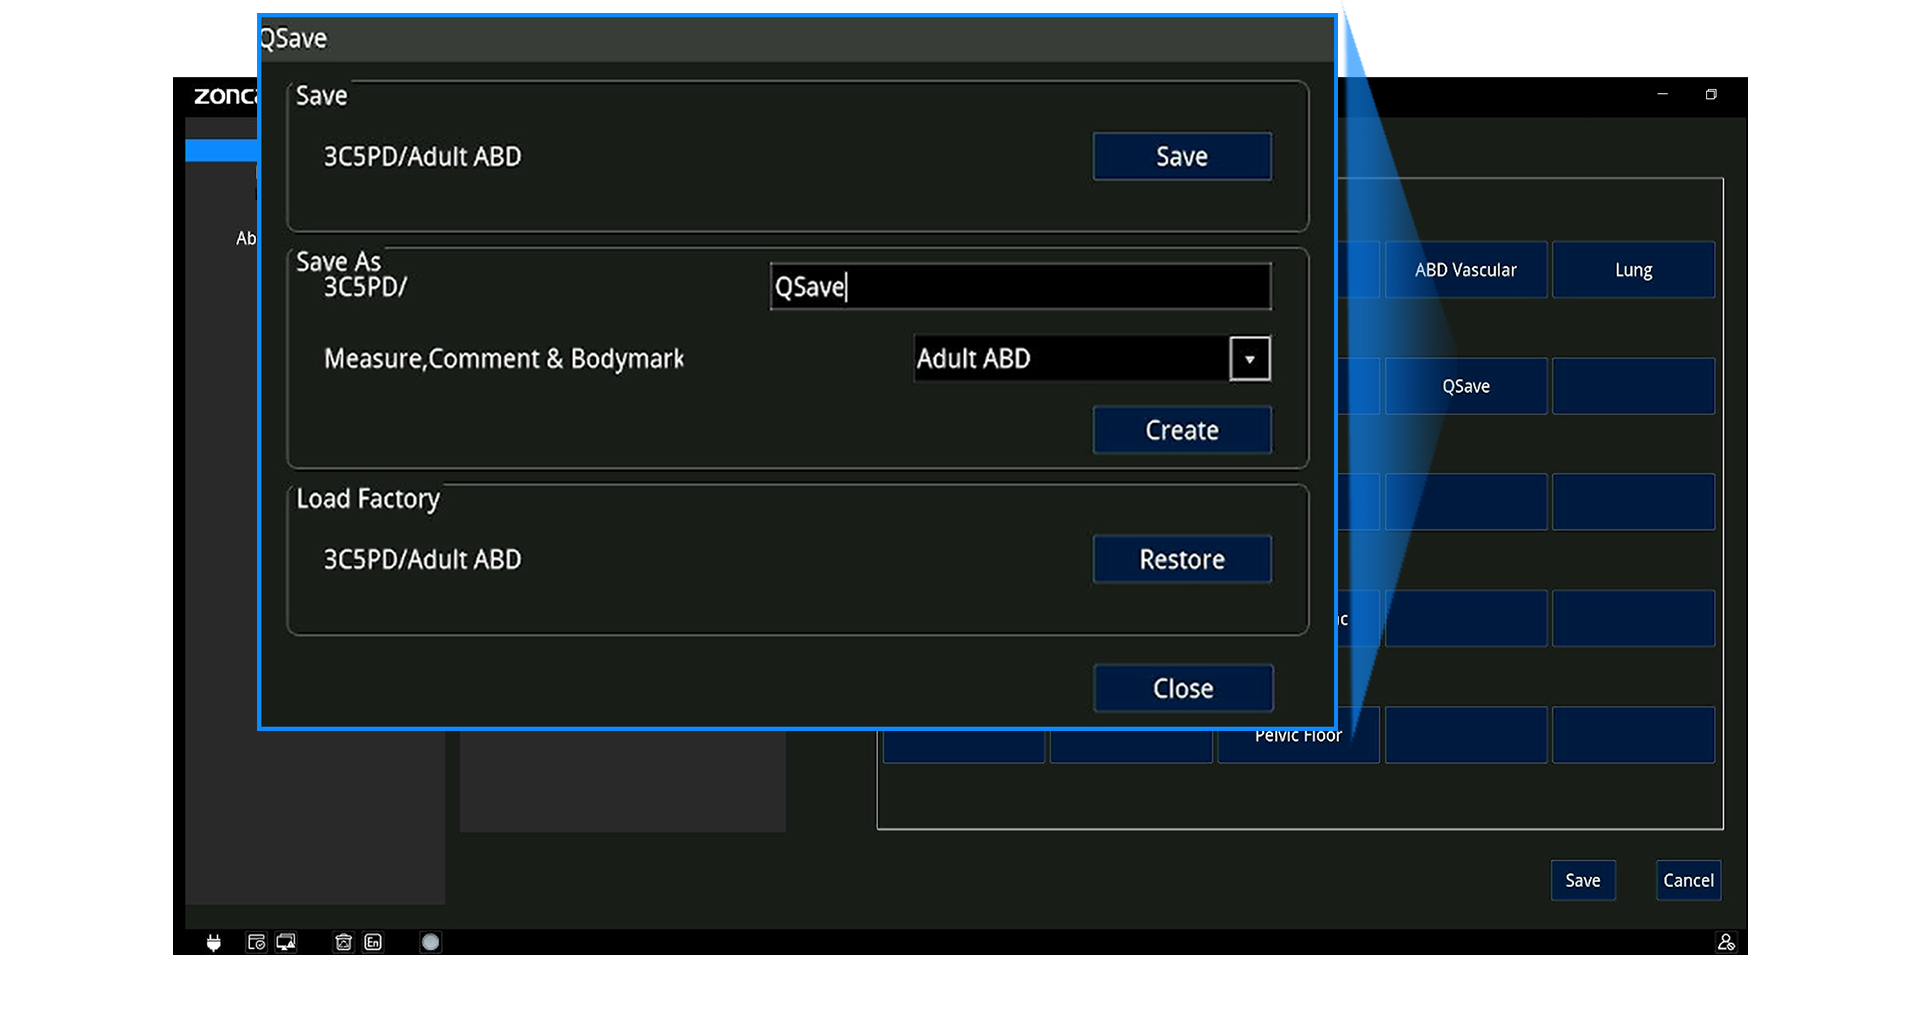

Panel ergonómico con trackball, TGC de 8 segmentos y teclas programables (Q1–Q4)

Almacenamiento, Datos y Conectividad

Formatos: RAW, DICOM, JPG, BMP, TIFF, AVI, MP4

DICOM 3.0 (Storage, Worklist, MPPS, Query/Retrieve, etc.)

Wi-Fi, Bluetooth, LAN, envío a PC

Teleconsulta remota, control inverso y docencia en vivo

Informes exportables a PDF (con opción de ocultar datos del paciente)